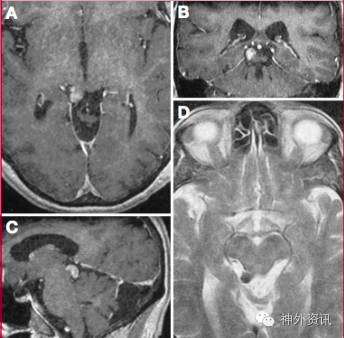

神经轴钙化性假瘤(calcifying psedoneoplasms of the neuraxis , CAPNON)又称中枢神经系统纤维骨病变,是神经系统罕见的非肿瘤性钙化灶,可发生于神经系统任何部位。1978年由Rhodes和Davis首次在尸检中描述该疾病[1],国外已报道59例[2],国内仅报道8例。但至今对于其病因及自然发展过程等知之甚少。尽管存在诸多不明确,但文献中多认为是一个缓慢生长的反应性过程,而非肿瘤性病变[3]。CAPNON的发病年龄为6-67岁不等,男性偏多,男女比例约为1.92:1。颅内CAPNON中,大部分病灶发生于轴外(66.3%,图5),椎管内则以硬膜外多见(81.48%,图6)[2]。

影像学特征:CAPNON影像学检查中,CT上表现为实质性钙化团块,MRI上通常表现为T1WI和T2WI呈低信号,无明显强化或边缘轻度强化肿块,不伴有周围水肿[2,4,5]。Shrier等报道的1例轴外枕骨大孔区肿块显示了类似脑膜瘤样的强化[6](图 7)。Guilherme等报道的1例四叠体区CAPNON,表现为T2均匀低信号,增强后明显强化[7](图8)。Duque等报道的4例均无明显增强,病灶周围也无明显的水肿[2]。但鉴于目前的文献大多缺少完整影像学资料,其特征表现仍需进一步探究。本例当地医院就诊时直接做了MRI,无法了解其CT表现的特征,影像学表现为不规则囊实性占位,与文献报道的病例少见囊性成分不同。但就术中所见,后部病变应为钙化或骨化的高密度肿块。

图7. 枕骨大孔区CAPNON,表现为类似于脑膜瘤样强化。

图8. 四叠体区CAPNON,表现为T2均匀低信号,增强后明显强化。